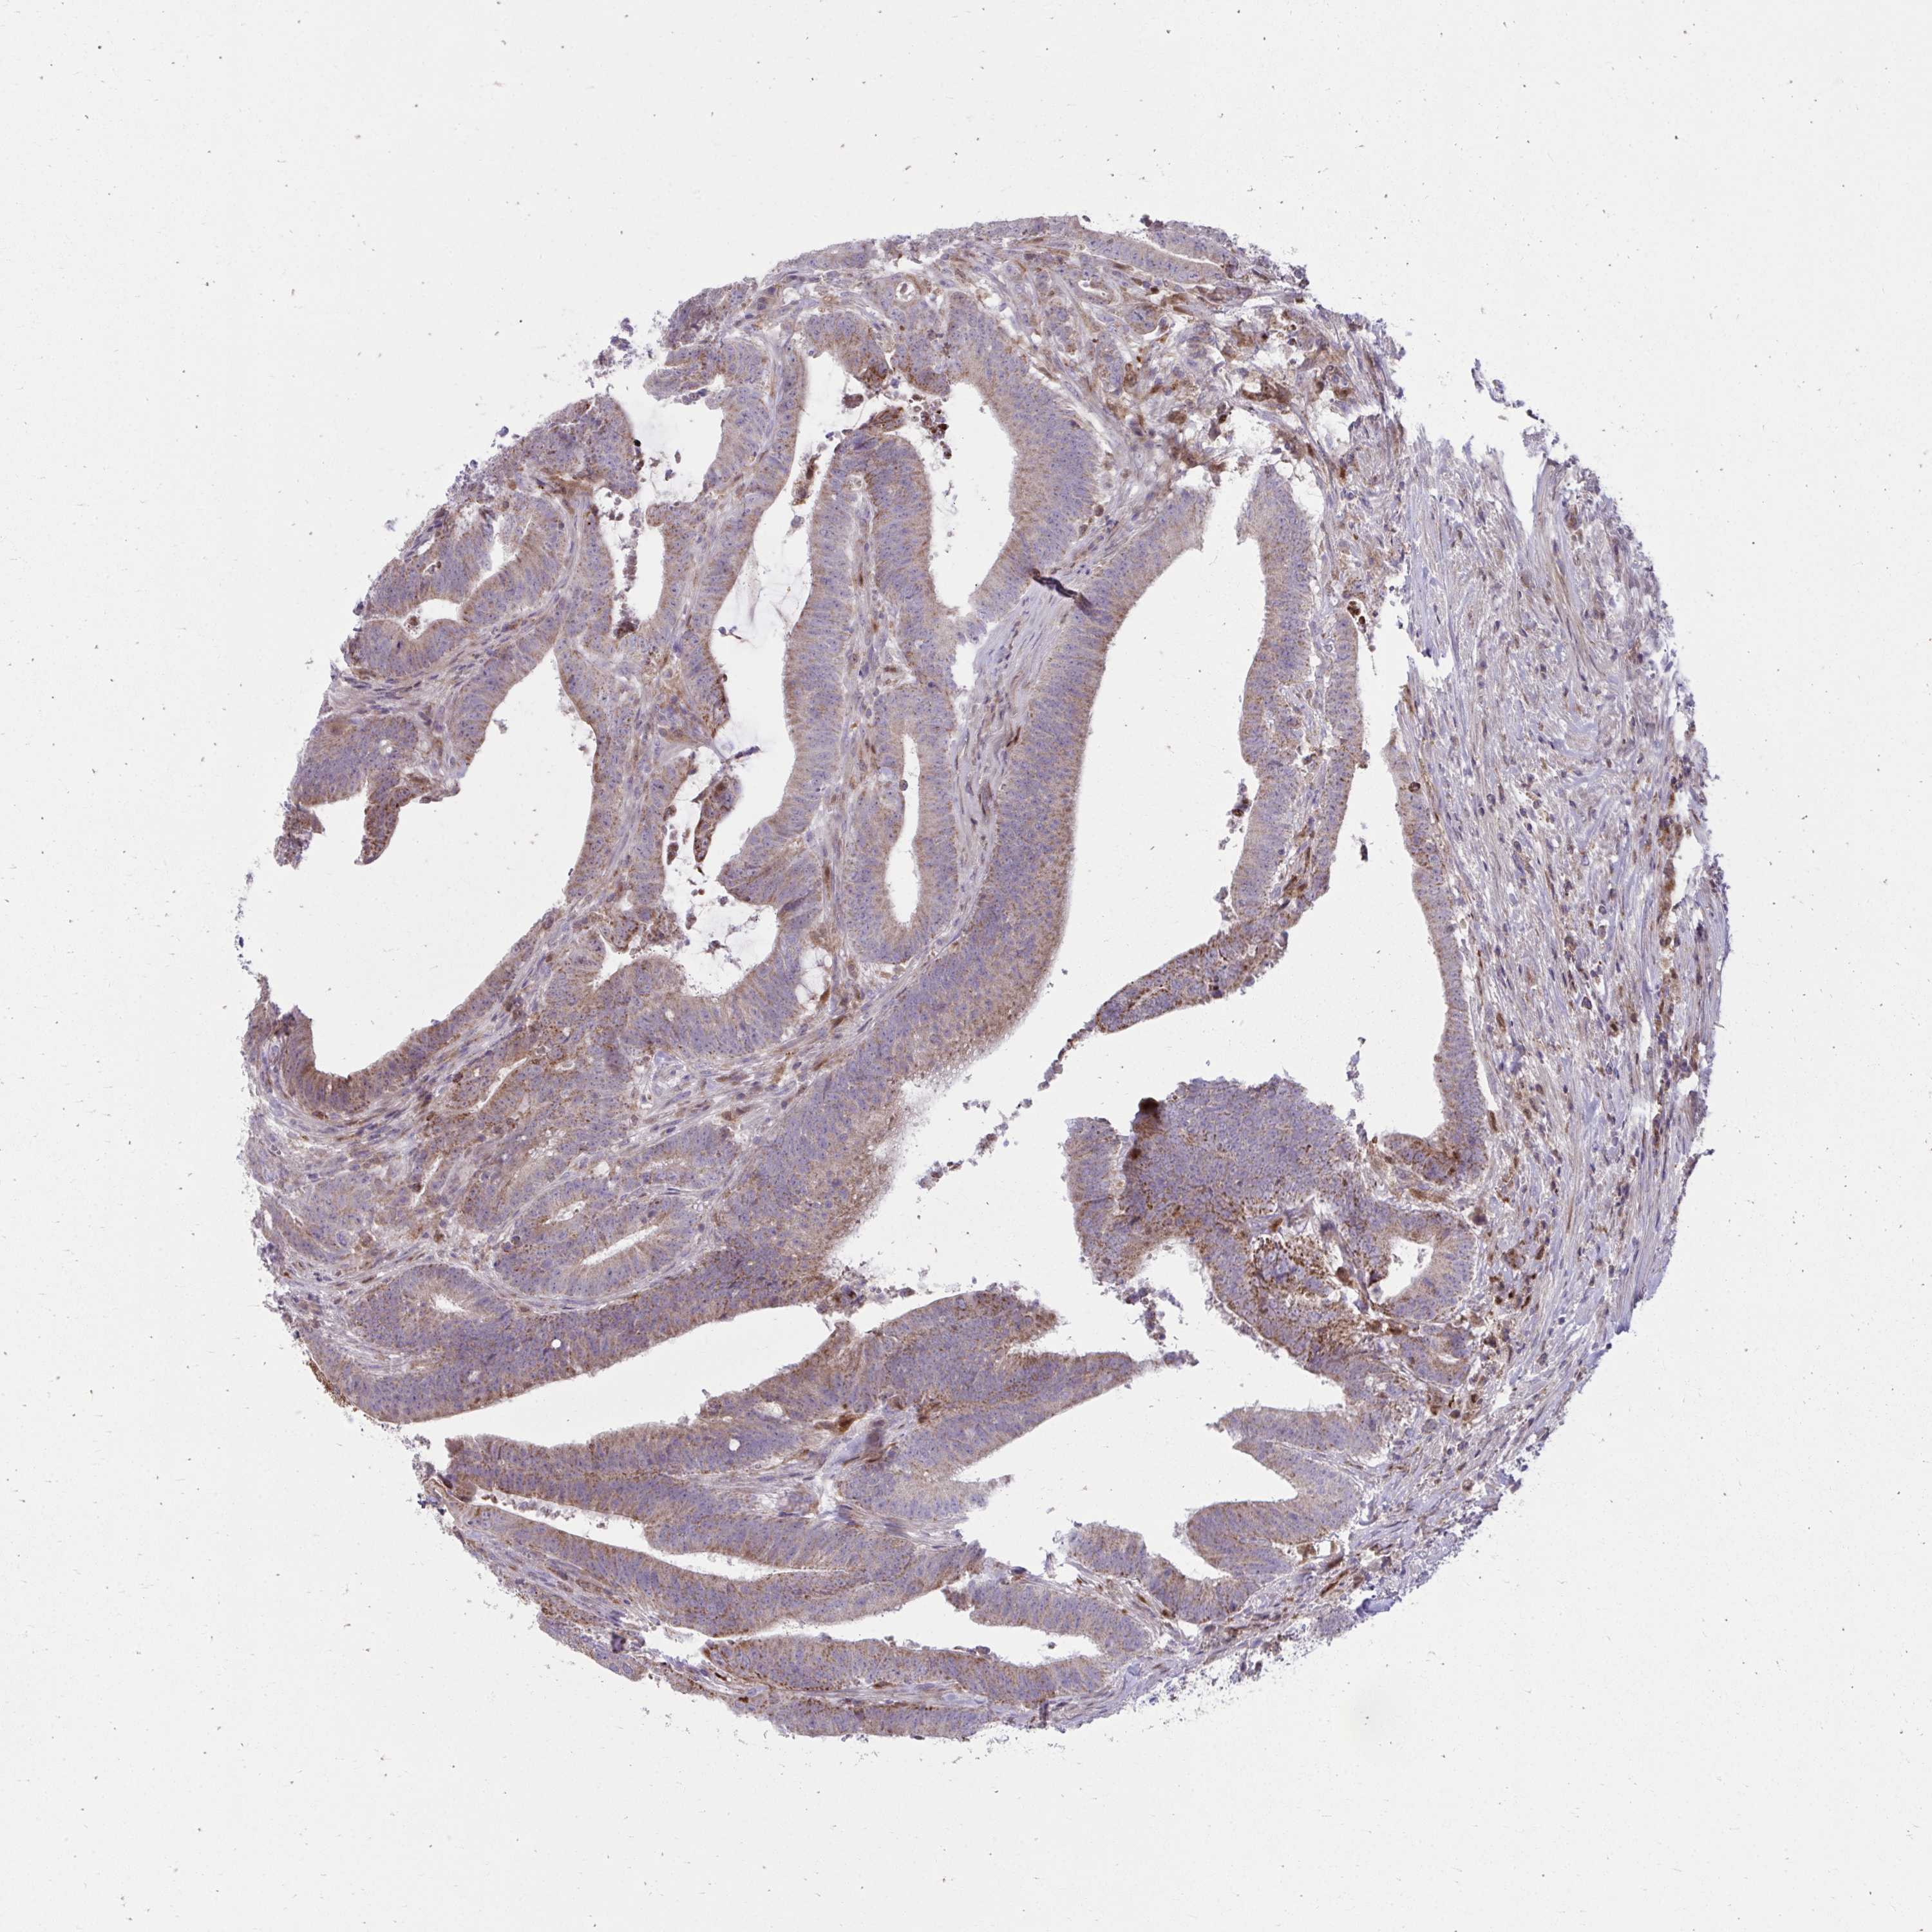

CANCER COLORECTAL CANCER Show tissue menu

Colorectal cancer

Colon adenocarcinoma